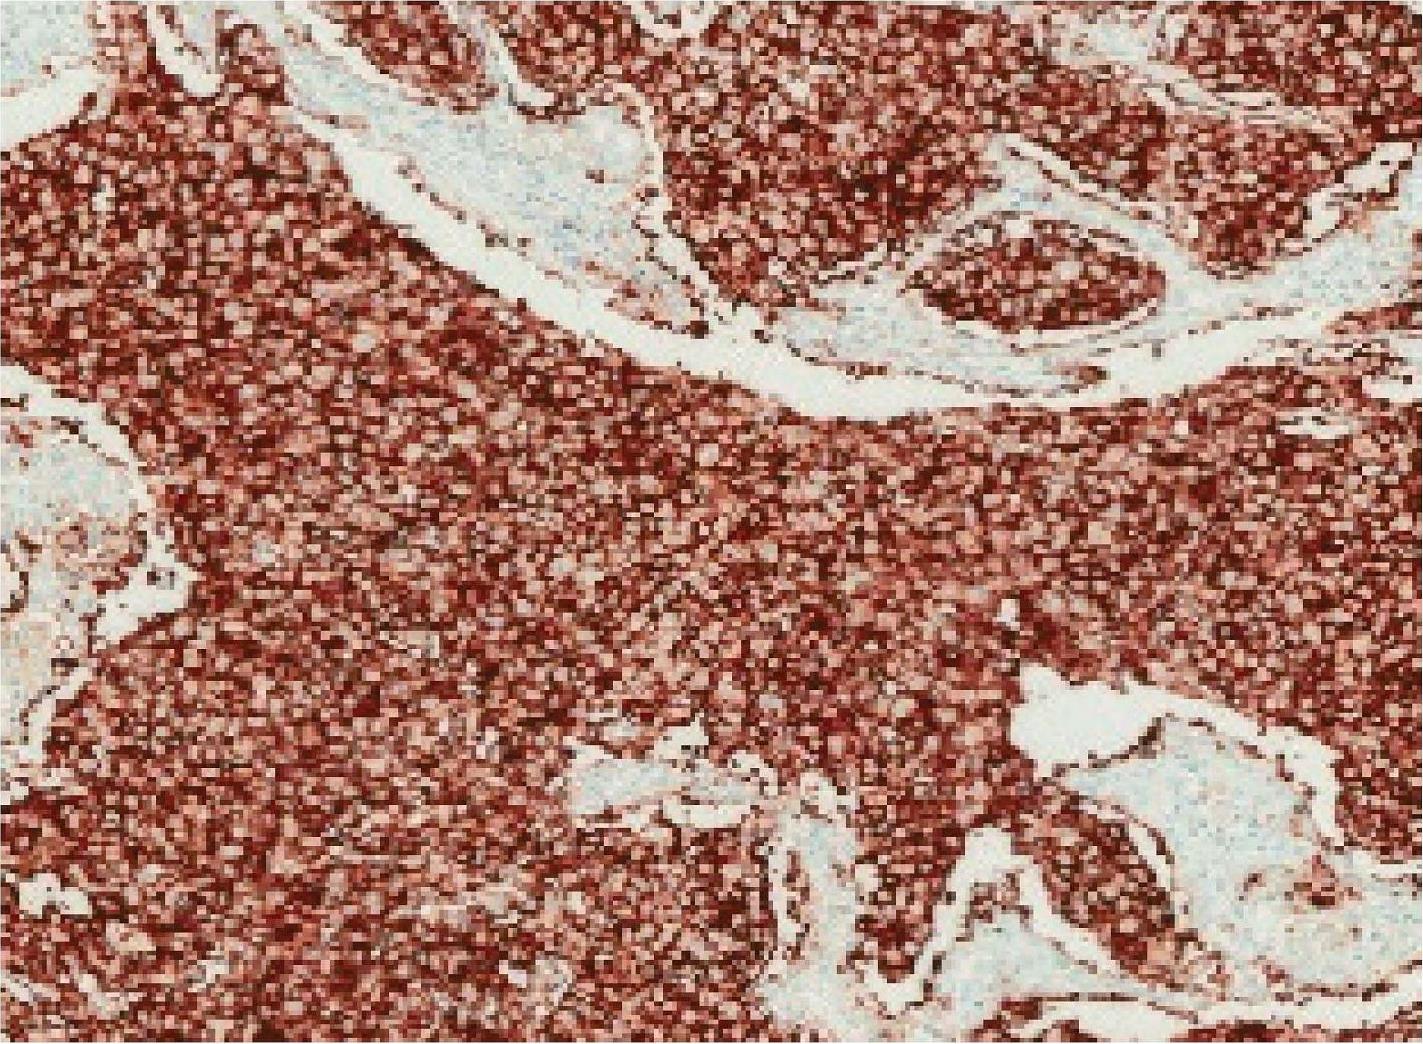

28-8克隆号检测平台及判读标准均与22C3相同,但关注的表达数值区间不同。该抗体PD-L1采用TC值计算,阈值分别为1%≤TC评分<5%、5%≤TC评分<10%、TC评分≥10%。图2-6所示为NSCLC PD-L1 (28-8)免疫组织化学染色图,TC评分为0;图2-7所示为NSCLC PD-L1 (28-8)免疫组织化学染色图,1%≤TC评分<5%;图2-8所示为NSCLC PD-L1 (28-8)免疫组织化学染色图,5%≤TC评分<10%;图2-9所示为NSCLC PD-L1 (28-8)免疫组织化学染色图,TC评分≥10%。

图2-9 NSCLC PD-L1 (28-8)免疫组织化学染色图(×200),TC评分≥10% [6]